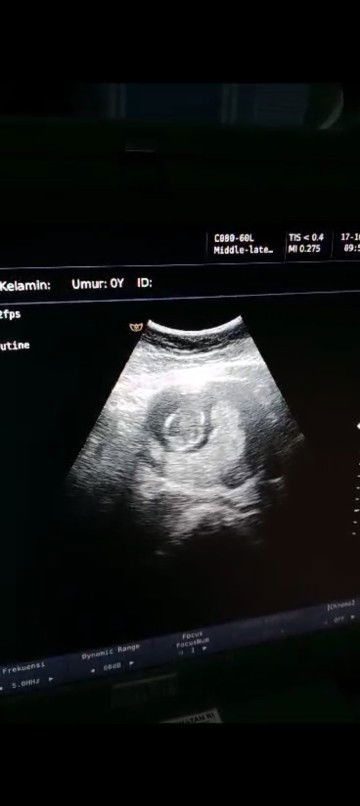

Usg 14 minggu apakah yg dibawah itu plasenta?

Apakah termaksud plasenta previa? Atau letak nya dibawah? Apakah bisa berubah🥺solusinya apa bund? Ovt bgt ini ##Sharing_dong_Bund #bantujawab #SeriusTanya #ingintahu

kata dokternya gimana bun? plasentanya dibawah atau gimana? aku alumni plasenta Previa total bun, di diagnosa pas usia 32 weeks untuk usia segitu udah kecil kemungkinannya untuk bergeser bun & kalo udah di diagnosa PPT (plasenta Previa total) itu harus bener bener bedrest jangan kecapean, stress nanti ngaruh ke bayinya, kalo usia 14 Minggu masih banyak kemungkinan untuk bergeser itu bun dengan seiringnya bertambah bbjnya

Baca lagisama bund aku juga plasenta Previa atau di bawah di jalan lahir, tapi kata dokter ini masih bisa lahiran normal, nanti juga plasenta bakalan naik ketika janin mulai membesar, kata dokter gausa khawatir sih tenang aja,, yg penting usg rutin sesuai anjuran dokter misalkan di tm1,tm2 dan tm3 bun.. aku juga sempet ovt..

Baca lagiEngga apa apa bund, saya hamil 15 minggu kata dokter plasenta di bawah masih wajar, nanti memastikannya harus 25 week keatas, blm bisa disebut plasenta previa, karna seiring berjalan waktu plasenta bisa mutar/ naik ya. Berfikir positif selalu🥰

pengalamanku dlu hmil anak prtama plasenta dibawah tp tdk mnutup jln lhr alhamdulillah lahiran normal untuk plasenta previa itu artinya plasenta mnutupi sluruh jln lhir bysa ditandai dgn flek flek